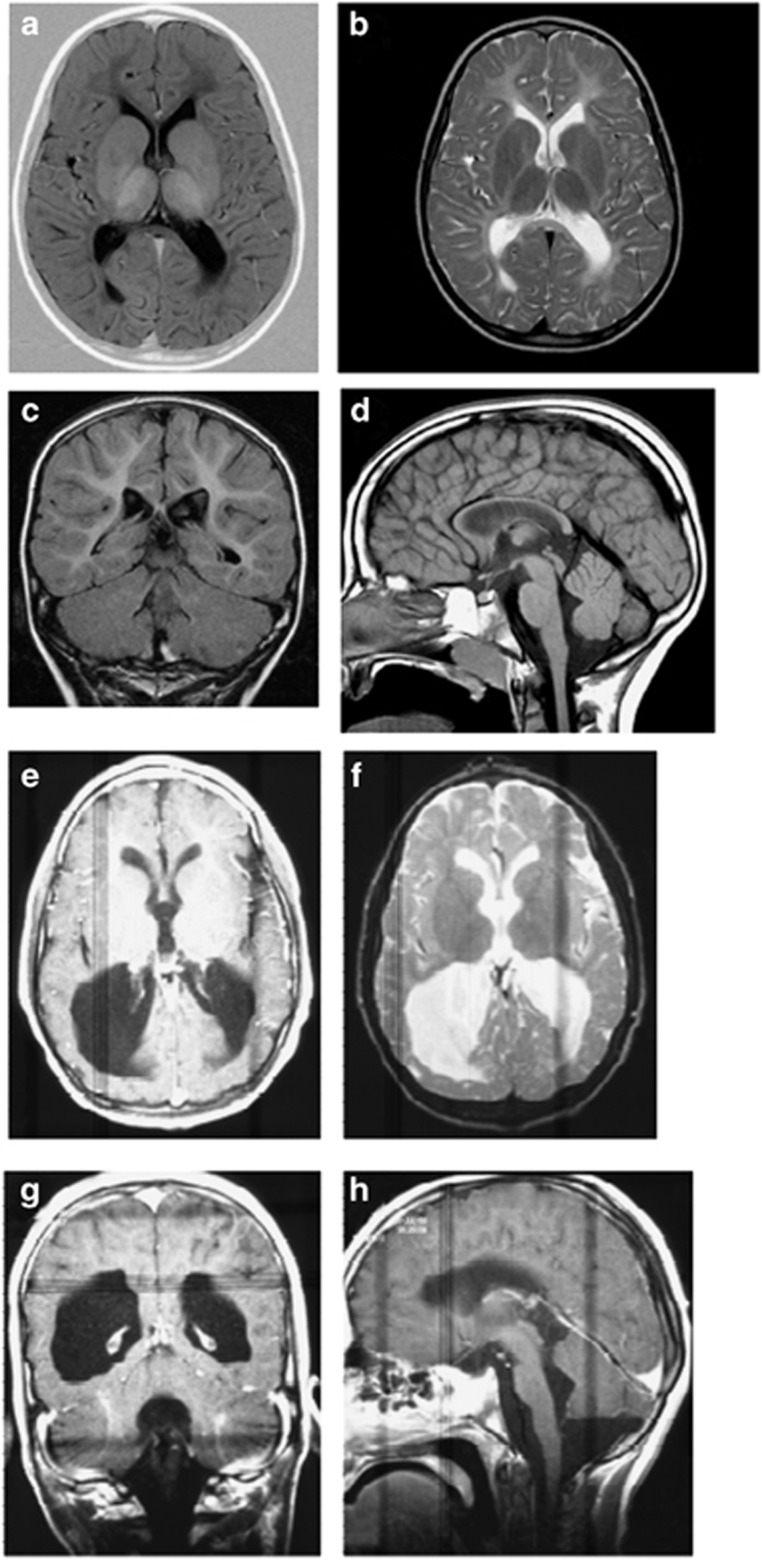

Normal investigations included creatine kinase, blood lactate, thyroid function tests, liver function tests, urine amino and organic acids, oligosaccharides and glycosaminoglycans, plasma very long chain fatty acids, serum transferrin isoforms, biotinidase assay, white blood cell lysosomal enzymes, karyotype, and fragile X testing. A brain MRI scan at 5½ years of age showed marked thinning of the corpus callosum, hypomyelination of the dorsal brainstem, internal capsules and deep white matter, with high T2 signal throughout the periventricular deep white matter. On the fluid-attenuated inversion recovery (FLAIR) sequences used in magnetic resonance imaging, the central white matter was hyperintense when compared to the more peripheral areas of non-myelination, confirming that there appeared to be a dys- or de-myelinating process centrally and non-myelination of the periphery (Figure 1). The findings were suggestive of Pelizaeus–Merzbacher disease. Sequencing of PLP1 only revealed a 3′UTR polymorphism (NM_000533.4 (PLP1_v001): c.*102C>T), and GJC2 sequencing was normal. A repeat MRI scan at 15 years of age showed that the white matter changes had been relatively stable, indicating arrest of myelination that had shown little progression over the years. The white matter volume was markedly reduced within both cerebral hemispheres and accompanied by prominent extra-axial spaces and ex vacuo dilation of the lateral and third ventricles, which had increased slightly in size from the previous scan.

Figure 1.

MRI scan of Patient 1 at age 5½ years. (a) Axial T1 IR (inversion recovery) – low signal in white matter consistent with hypomyelination; (b) Axial T2- diffuse white matter hyperintensity consistent with hypomyelination (most important image); (c) Coronal T2 FLAIR_ high signal white matter; (d) Sagittal T1 – thin corpus callosum consistent with white matter volume loss. (e) Axial T1 and (f) axial T2 (inverted contrast) – enhanced cerebrospinal fluid spaces associated with hypomyelination and generalised cortical thinning; (g) Coronal T2 – ventricular dilatation; (h) Sagittal T1 – hypoplasia of the corpus callosum with only the rostral part demonstrable.